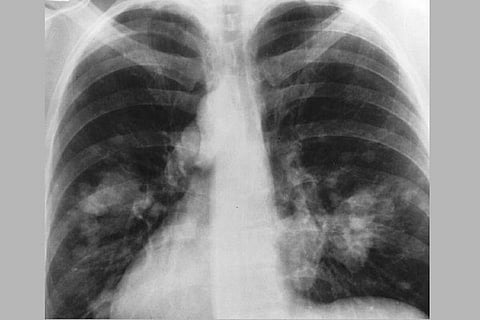

All COVID-19 patients shall be screened for TB depending on these factors: if they have fever or cough for more than two weeks, weight loss and night sweats. Any patient with one of these symptoms shall be tested. A COVID-19 patient with abnormality in chest X-ray shall also be tested for TB.